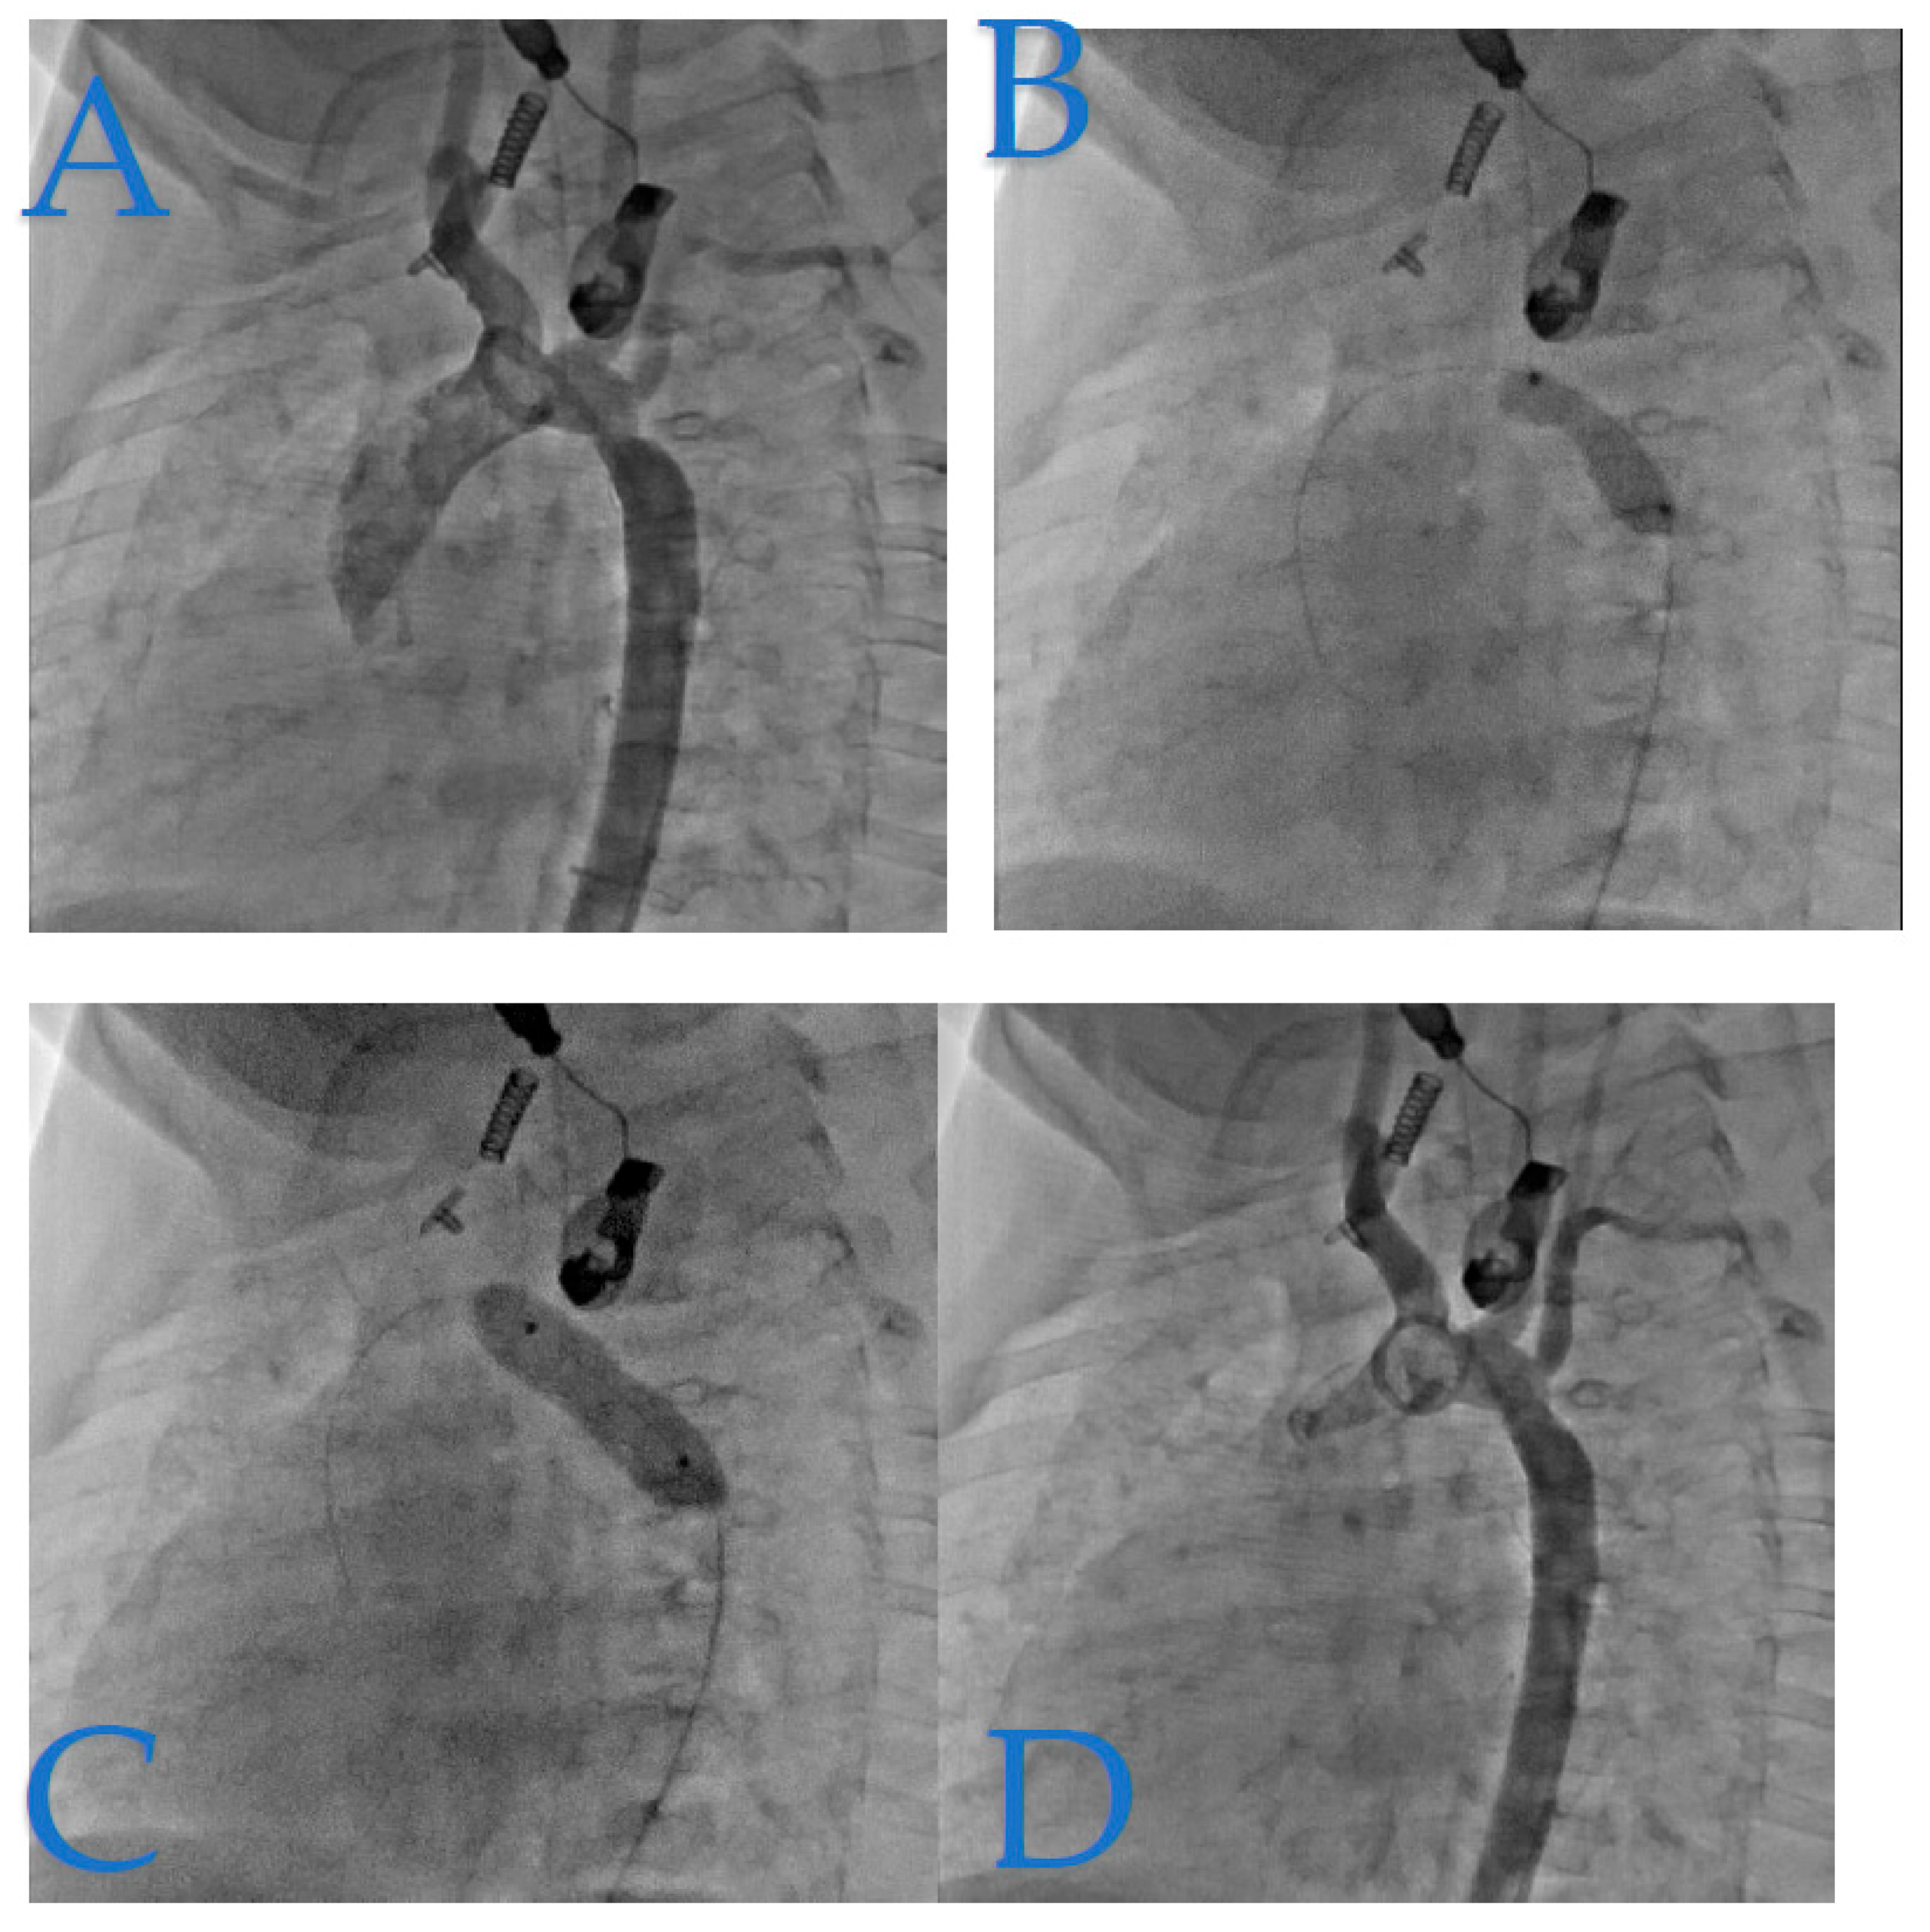

Figure 4 presents a case of isthmic recoarctation in a 6-month-old infant weighing 6.7 kg. The patient had undergone coarctation repair at 8 days of life through an extended end-to-end anastomosis via a left thoracotomy. However, immediate recoarctation occurred due to a clot on the anastomosis.

Figure 4. Pediatric Isthmic Recoarctation Case. (A): In this image, we observe a notable feature: a notch on the dilatation balloon. This notch reflects a transrecoarctation gradient of 20 mmHg. (B): This part of the figure, which was initially missing, provides a close-up view of the notch on the dilatation balloon, highlighting the details of the recoarctation. (C): The notch was effectively and completely lifted by a 7x20 mm Tyshak balloon. (D): Subsequent angiography reveals good angiographic and hemodynamic results, with a residual gradient of just 9 mmHg.